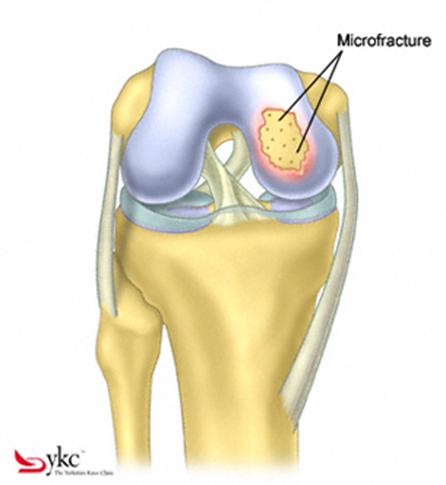

Fig.21. Diagrama unei leziuni cartilaginoase.

Fig.23. Diagrama microfracturi: a. Leziunea; b. Rezultatul interventiei.

Chirurgul trebuie sa fie foarte atent atunci cand examineaza posteriorul condililor femurali. Daca se semnaleaza orice vatamare/rana/deteriorare pe suprafetele articulare, trebuie sa se cerceteze atent calitatea cartilagiului. Orice flapsuri instabile sunt inlaturate prin folosirea unui aparat de ras electric artroscopic sau curette. Apoi, un curette este folosit pentru a debrida stratul de cartilagiu calcifiat de la baza in toata grosimea defectului. Acest pas se bazeaza pe activitatea lui Frisbi, care a demonstrat vindecarea suprafetei articulare superioare la un cal, cand stratul cartilagiului calcifiat este indepartat. Cand indepartam stratul cartilagiului calcifiat, in general nu se foloseste un aparat de ras. Cu un aparat de ras este dificil de controlat cantitatea de os eliminat, si este posibil ca osul subcondral sa fie afectat.

Dupa indepartarea cu succes a stratului de cartilaj calcifiat, o andrea este folosita pentru a face mai multe gauri mici (mirofracturi) in osul expus al defectului condral aflate la distanta de 1-2 mm. Trebuie lasata o punte de oase potrivita intre gauri. Tehnica de microfracturi are numeroase avantaje fata de foraj. Mai intai de toate, creaza o leziune termala mai mica. Mai mult, cu microfracturi, chirurgul este capabil sa intre in zonele dificile ale suprafetei articulare cu un control mai bun asupra adancimii de patrundere. La finalizarea microfracturii, o suprafata aspra este generata pentru a aderenta cheagului de sange care contine celule mezenchimale nediferentiate de la osul subcondral. Trebuie avut grija ca cele mai marginase parti ale leziuni sa fie patrunse de andrea pentru a ajuta la vindecarea tesutului reparator la imprejmuirea suprafetei articulare. Odata ce microfractura este finalizata, pompa artroscopica este oprita pentru a se asigura ca sangerarea maduvei curge din gaurile mici umpland defectul.[54]